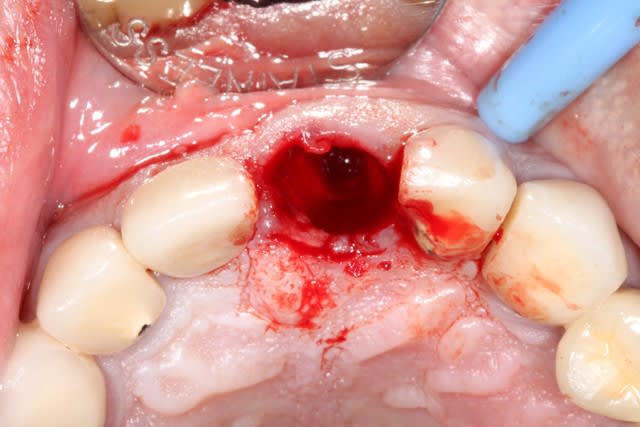

2/ extraction + forage lingualé

3/ pose d'un implant Dentium SuperLine 5/14 en ménageant un espace avec l'os vestibulaire

4/ comblement avec de l'osteon de l'espace vestibulaire, mais aussi d'un autre espace

cet espace est une poche sous périostée qui est créé en vestibulaire de l'os vestibulaire, il faut évidemment ne pas déchirer le périoste.